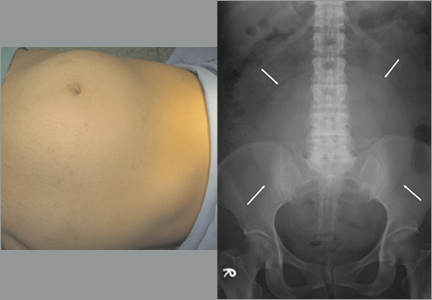

On physical examination, we noted an enlarged, palpable, fixed, firm mass in the lower abdomen (FIGURE 1A). We also noted considerably decreased bowel sounds on auscultation. A kidney, ureter, and bladder (KUB) x-ray revealed a soft tissue mass shadow in the pelvis (FIGURE 1B).